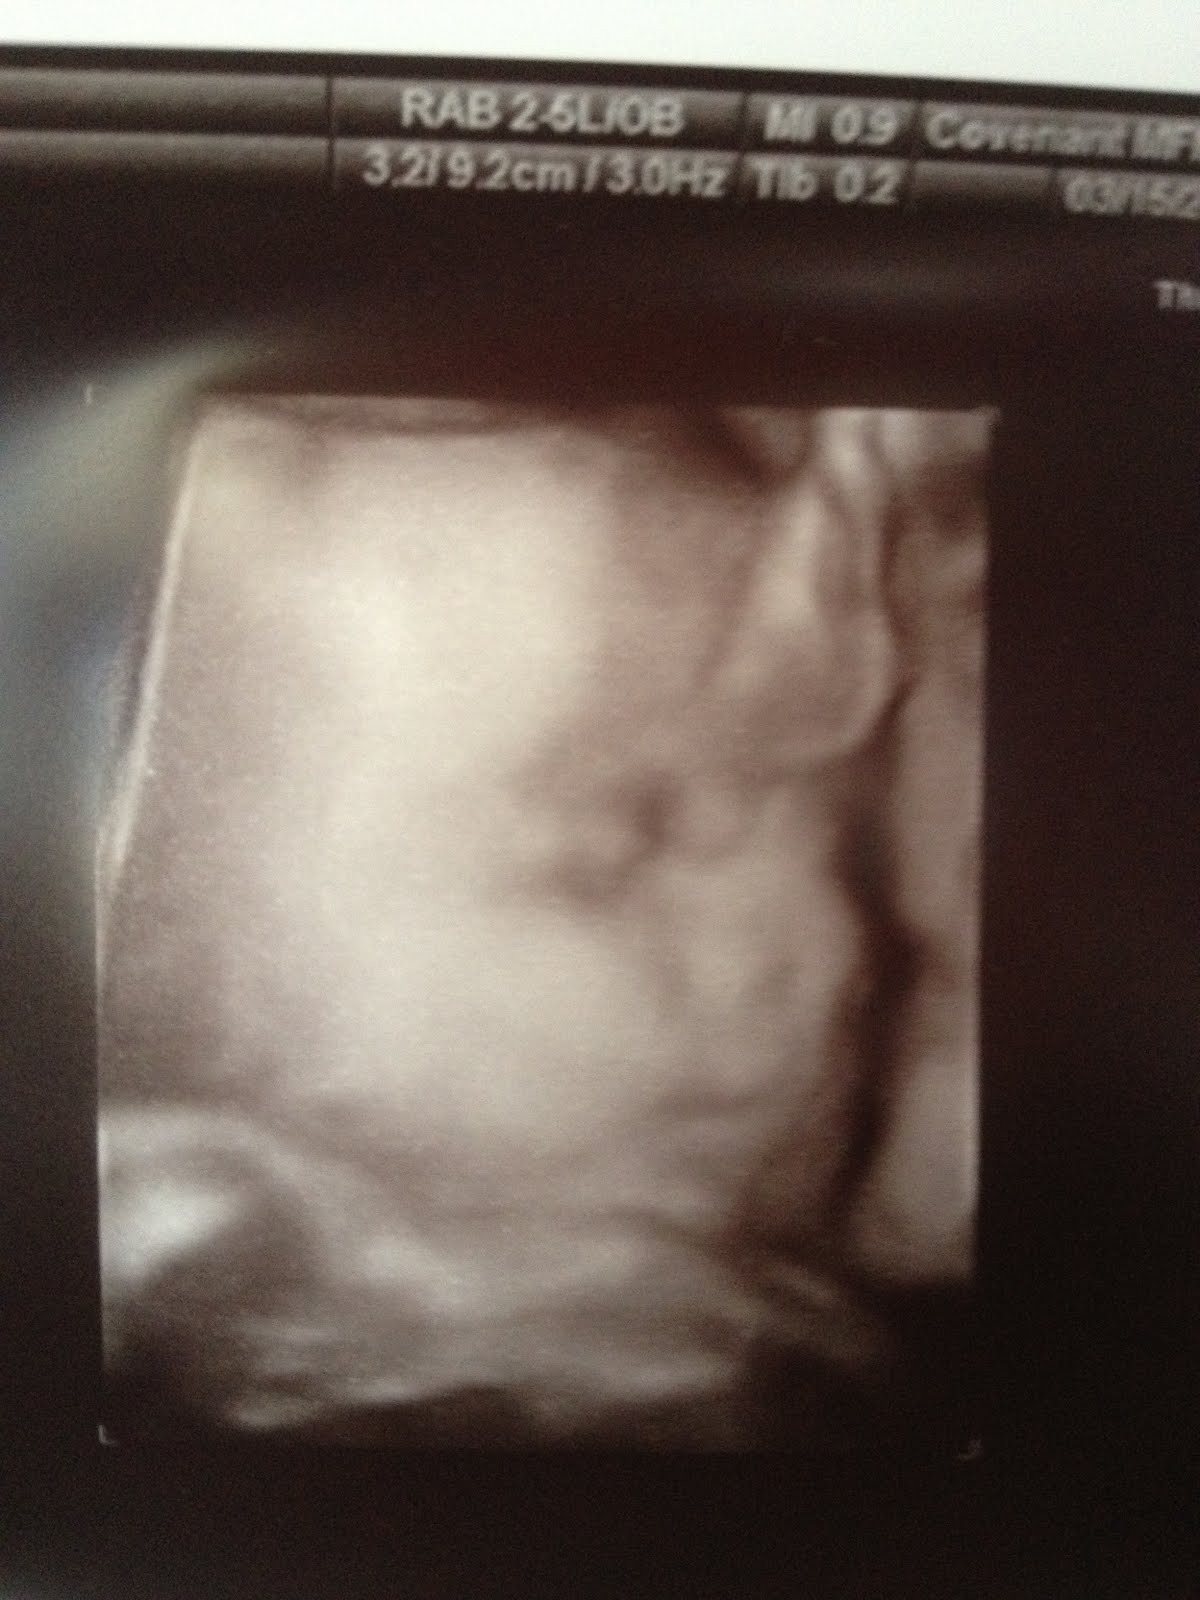

Based on her measurements they guessed she weighed about 2lbs 10 ounces. I can't believe she is already nearly 3 whole pounds. The first thing we all noticed was her little nose. It just seemed to stick out to us. I can't wait to kiss it!!

Another huge PRAISE, my cervix is still measure long and the cerclage seems to be holding well. My doctor said other than coming in for my weekly progesterone shots (which feel like a bee sting times 10) he would only check Pyper and I one more time next month and then take the cerclage out at 36 weeks. YIKES, this is flying by! I'm so thankful that everything looks well and I'm not restricted as much or having to do anything extreme this time. God is so good! Here are a few pictures of our little princess!